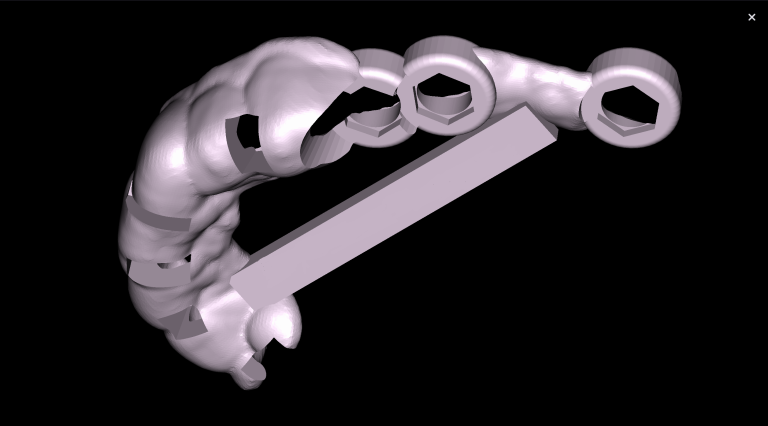

The decision has been made to perform immediate implant placement to replace teeth 24 (Universal 12) and 25 (Universal 13).The optimal position of the future implant is planned by starting with intraoral scanning and importing digital models into the Diagnocat STL module

3D reconstruction created on the basis of DICOM and an intraoral scan in the Diagnocat STL module allows you to choose the optimal size and location of the implants

A template for guided implant surgery was planned and manufactured based on these digital models for the replacement of teeth 24 (Universal 12) and 25 (Universal 13)

Based on digital models, a virtual design of a template has been planned for the replacement of tooth 36 (Universal 19)